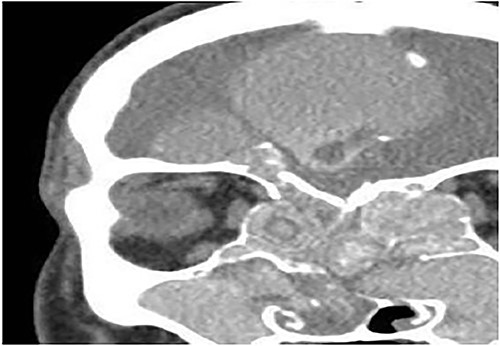

A 15-years-old male presented with bilateral nasal obstruction for a long time associated with nasal discharge, allergic nasal symptoms and headache. Endoscopic nasal examination revealed bilateral extensive nasal polyposis and mucin. CT scan (Fig. 7) and magnetic resonance imaging (MRI) scan (Fig. 8) of the paranasal sinuses confirmed the diagnosis of extensive bilateral allergic fungal pansinusitis with intraorbital and intracranial extradural extension. The patient underwent FESS, and all the polyps, mucin and fungal debris were removed from the sinuses. The patient continued on medical treatment and remained symptoms-free for 5 years follow-up.

Coronal CT paranasal sinuses shows heterogeneous opacities of the ethmoid and maxillary sinuses bilaterally. It is associated with complete opacification and extension through the widened ostiomeatal complex, obliterating the nasal cavities with polyposis. The ethmoid sinuses show expansion with lateral displacement and partial dehiscence of the lamina papyracea bilaterally. The roof of the right ethmoid sinus shows dehiscence with intracranial extension.